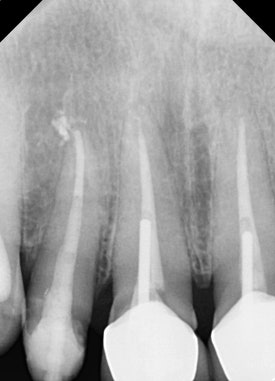

교정적/외과적 정출술을 시행하기 앞서

치아 상태에 대한 면밀한 조사가 필요합니다.

-

심각한 치아 염증이 없어야 합니다.

뿌리의 길이가 충분히 길어서, 치아를 밀어올리더라도 뼈 안에서 전체 치아를 지지해줄 충분한 길이가 남아있어야 합니다.

이 두 가지 조건을 충족시켜야

비로소 정출술을 시도할 수 있습니다.